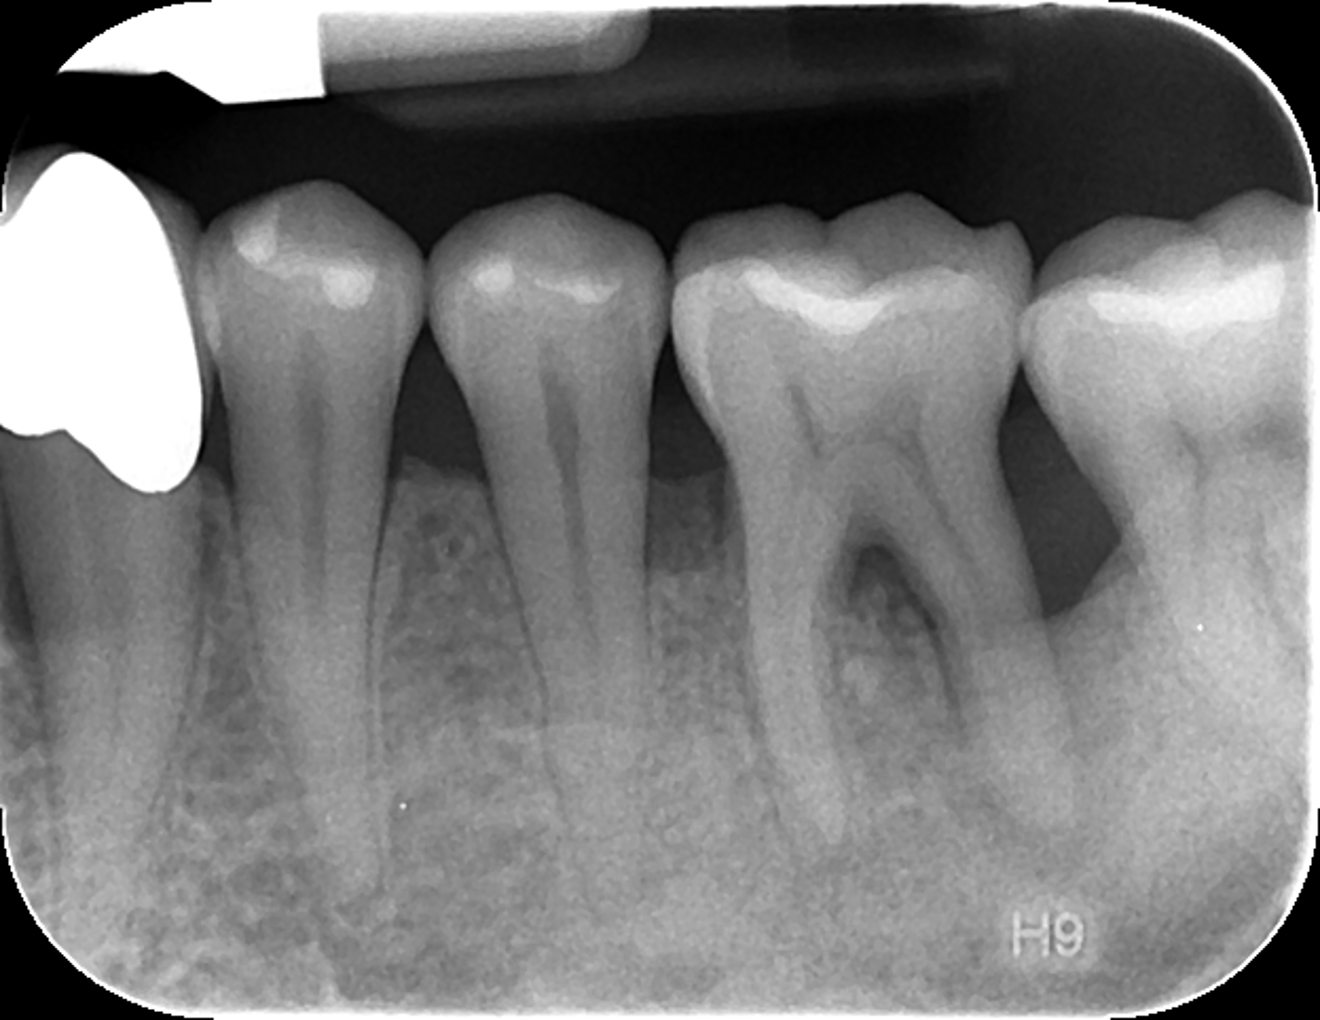

Fig. 6: Periapical radiograph of tooth #36 after treatment.

During the semi-annual dental examination, a panoramic radiograph was taken to enable a comparison of bone structure. A significant improvement in bone density was observed, especially around teeth #13, 36, 33, 43 and 47, where severe vertical bone loss was initially present. Clinical improvements were also noted, including inflammation-free gingivae with slight recession (Figs. 5 & 6).

An appropriately administered anti-infective therapy in combination with suitable antibiotic treatment resulted in a significant improvement in PPD. Clinical improvement was also observed: no swelling or redness in the gingival area and no more pain on biting. Subsequent re-evaluation appointments consistently showed improvement in both PPD and BOP, as well as at-home plaque control. The radiographic control images revealed bone defect filling, especially around the prognostically problematic teeth.